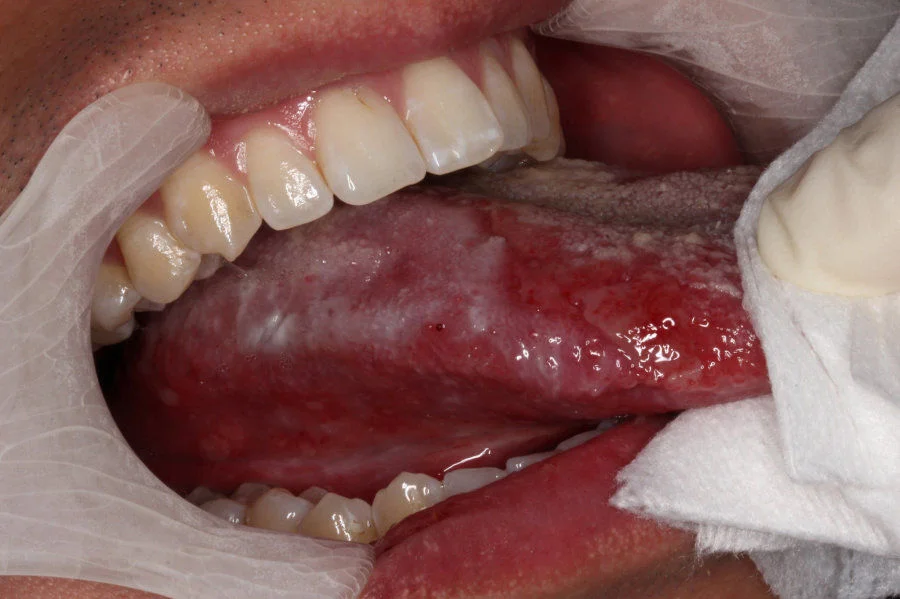

Oral cancer often develops from white patches clinically known as oral leukoplakia (OL) and oral lichenoid mucositis (OLM). These white patches may appear long before a diagnosis of oral cancer, and their early detection and continuous monitoring are crucial to prevent the development of cancer. However, it is sometimes challenging to predict which OL/OLM lesions will develop into oral cancers as the global risk rates of progression from OL/OLM to cancer vary from 0.4 to 40.8%.

Routine visitation and multiple biopsies are often scheduled during OL/OLM surveillance. In addition, patient monitoring may continue for many years leading to fatigue and lack of compliance with hospital appointments. Therefore, it will be better to determine the risk of cancer development in these patients on an individual basis to allow health professionals to use this information to formulate specific treatment and follow-up schedules for each patient.